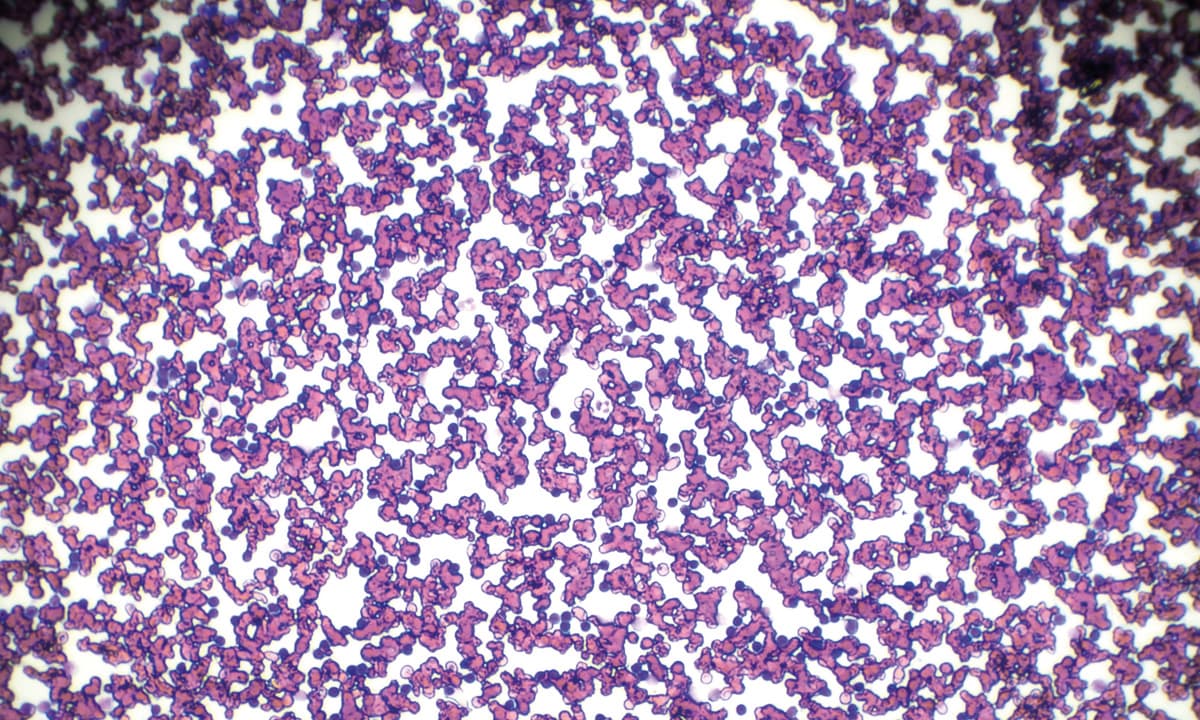

Die chronische lymphatische Leukämie (CLL) ist geprägt von konsekutiven Rückfällen. Schlussendlich entscheidet das Therapieansprechen über das Überleben der Patient:innen. In der randomisierten Phase-III-Studie ALPINE wurden Ibrutinib und Zanubrutinib head-to-head bei Patient:innen mit rezidivierter oder refraktärer chronischer lymphatischer Leukämie (CLL) gegeneinander verglichen und eine Überlegenheit von Zanubrutinib gezeigt.